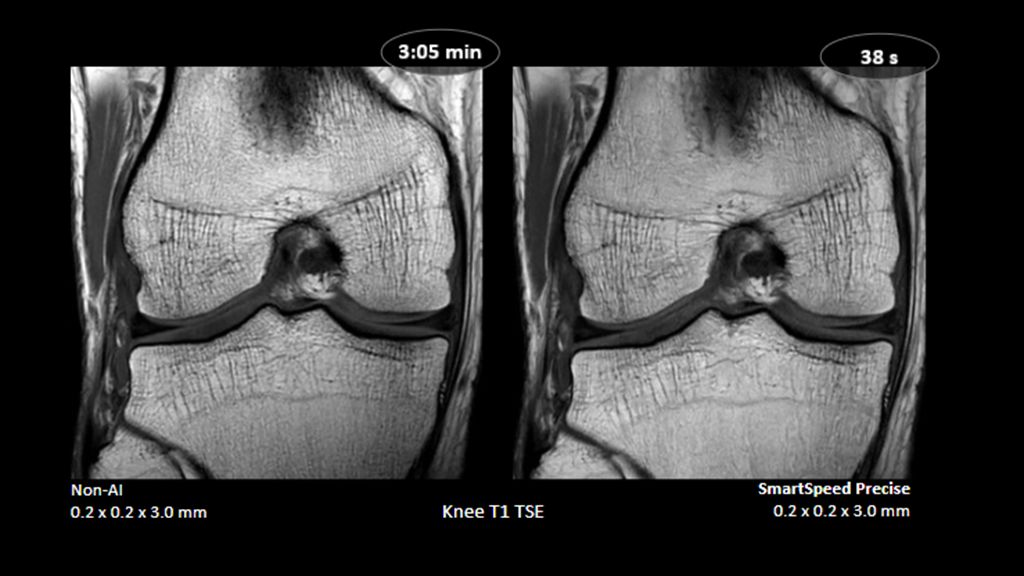

1. Compared to SENSE imaging, with no loss in image quality.

2. Reconstruction technology Compared to conventional (SENSE/ Compressed SENSE, SmartSpeed AI) imaging. Sharpness was evaluated with phantom scanning.